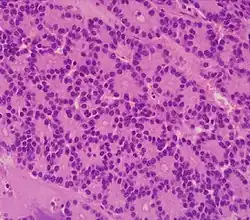

Pancreatic neuroendocrine tumor 5% Multiple nests of tumor cells

Gastrinoma